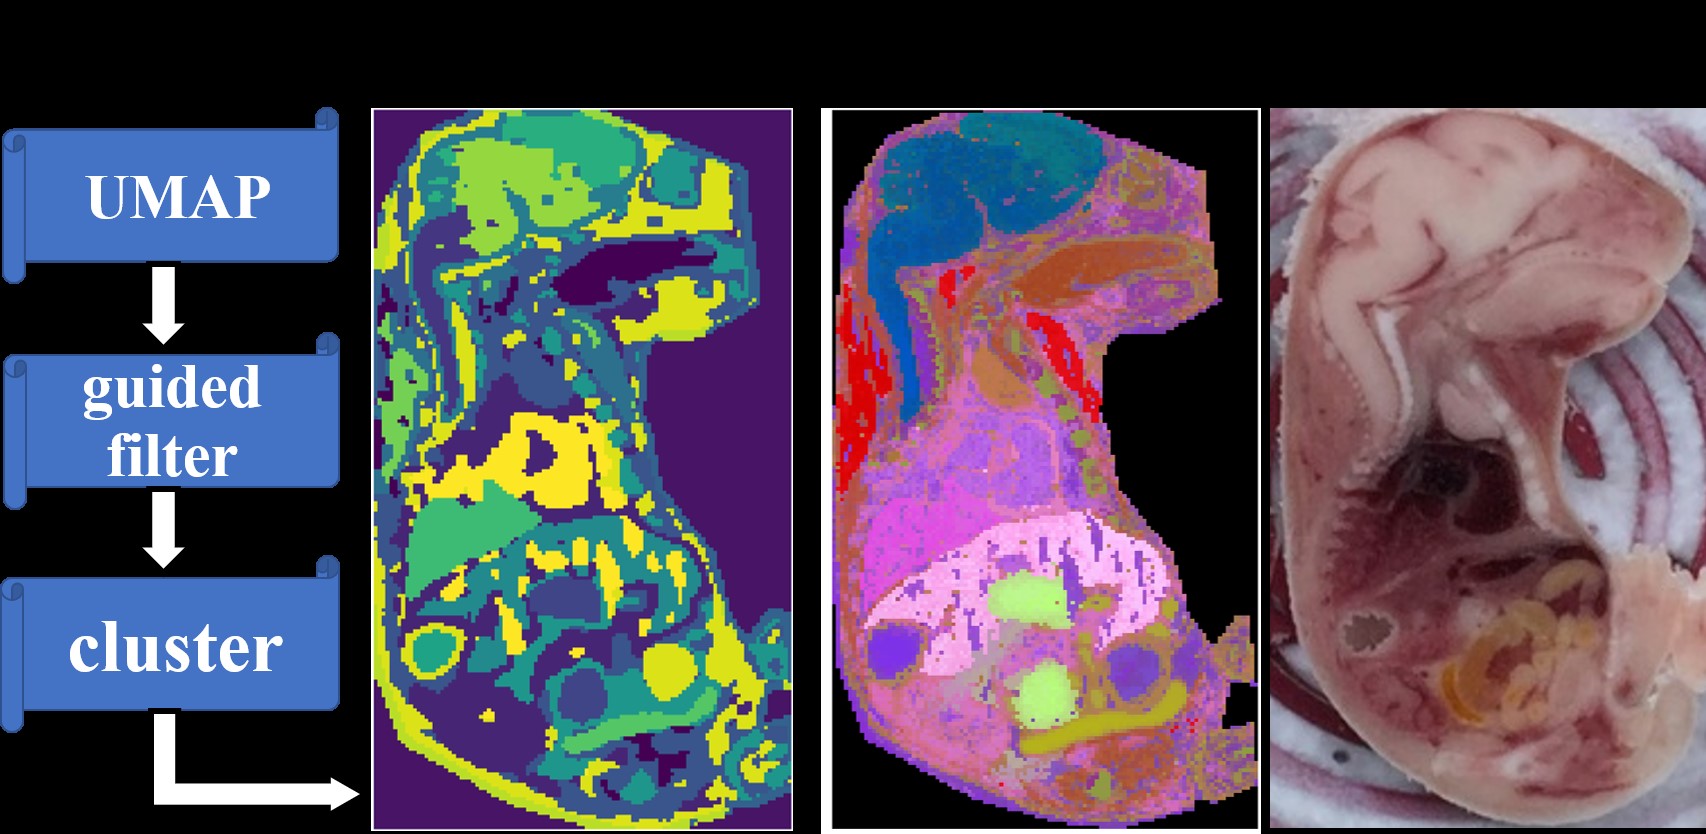

此外,课题组通过大量的实验分析,详细分析了数据滤波算法对MSI空间分割的影响,提出一种新型质谱成像空间分割流程,有效地提高了空间分割结果的可靠性。在目视检测、空间均匀性、时间成本和鲁棒性方面均优于其他传统方法。这项工作为评估和筛选药物/化学诱导的靶向器官,探索疾病进展和分子机制提供了有力的工具。该项工作于2021年3月8日发表在Analytical Chemistry上。

图3. 优化的MSI空间分割流程及其结果